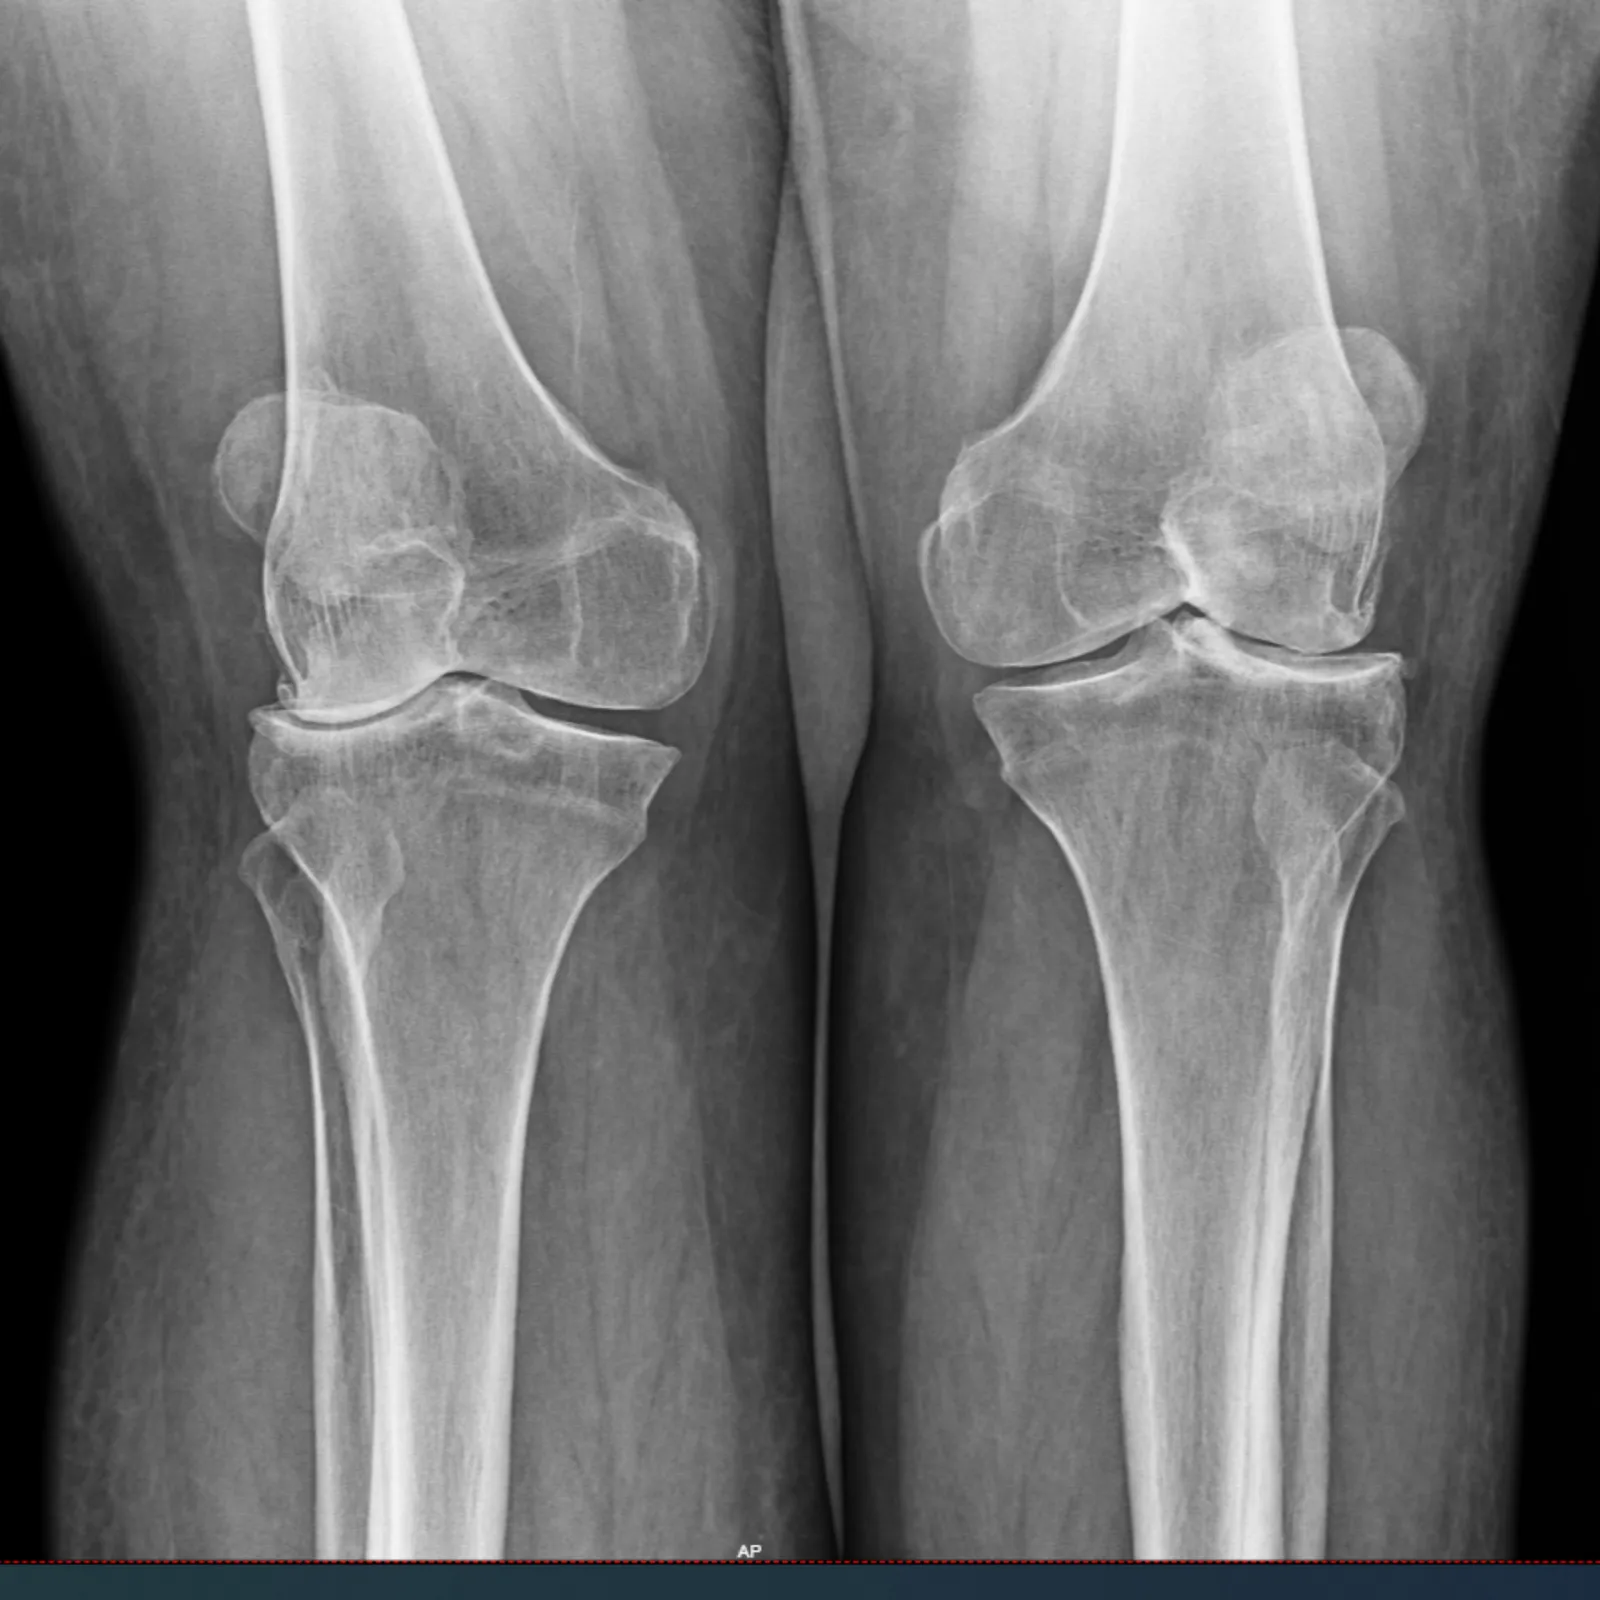

"This was my first time as a patient of Dr. Denehy. I had a prior right knee and hip replacement by Dr. Balthrop [retired]. My left knee was bone on bone and I was in terrible pain. During my visit, Dr. Denehy informed me I needed a knee replacement.